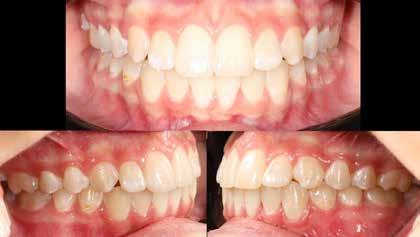

A vegyes fogazati kezelési célok a fogívek tágítása és a mandibula meziális irányú növekedésének a biztosítása volt. Fontos, hogy az ilyen típusú készülékeket nem csak éjszaka, hanem napközben is – amennyit csak lehet – hordani kell a minél hatékonyabb működés érdekében. A 18 hónapos első fázisú kezelésnek köszönhetően az alap kezelési célok megvalósultak, sikerült a class 1-es okklúziót beállítani (4-7. képek).

terséges harapásemelés pedig az alsó hatosokra, majd később a felső négyesekre került (8. kép). Az intermaxilláris elasztikus gumihúzás class-2-ess vektorú volt annak érdekében, hogy a disztálharapás korrekciója tökéletes legyen (9. kép). A harapást beállító elasztikus gumihúzásokat – mint minden kezelésnél –, ebben az esetben is folyamatosan, az egész kezelés alatt 24 órában (étkezések kivételével) viselte páciensünk.

A második Pitts-21 fix készülékes fázis ideje 16 hónap volt (10-12. képek)